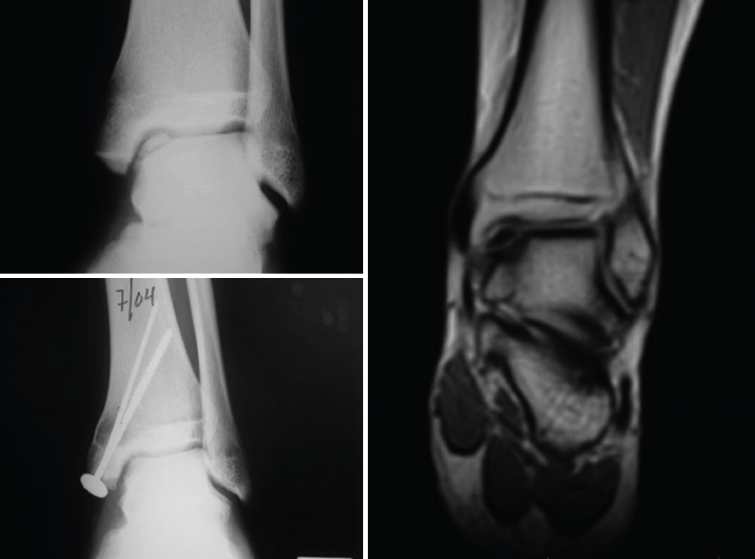

Patients with osteochondral defects of the ankle: results of the first patients with two years of follow-up

A study was made of the first 52 patients with osteochondral defects of the ankle treated with the ICC technique - most of them (34 patients) in the Clínica CEMTRO(35). One of the particularities of the chondrocyte implant procedure in the ankle is that in most cases an osteotomy is first required in order to access the lesion. Although in some patients the defect was more superficial, in the majority of cases (up to 96%) the defect was of an osteochondral nature. In 35% of the patients the lesion was over 4 mm in depth, and a cancellous bone graft was required, obtained from the osteotomy itself, above the subchondral bone, with placement of the membrane with the cells over this graft.

The short/middle term outcomes of the treated patients were very satisfactory. Both pain, evaluated by means of the VAS, and ankle function assessed by the American Orthopedic Foot and Ankle Society (AOFAS) score(36), improved significantly one year after treatment, and this improvement persisted at least one year later. The percentage of patients with good or excellent outcomes after 12 months was 75%, and this figure further increased to 79.2% at 24 months post-treatment.

[[{"fid":"4553","view_mode":"default","fields":{"format":"default","alignment":""},"type":"media","field_deltas":{"22":{"format":"default","alignment":""}},"link_text":null,"attributes":{"class":"media-element file-default","data-delta":"22"}}]]

The clinical results were correlated to the radiological findings, revealing correct graft integration and regeneration of the cartilage (Figure 19).

[[{"fid":"4554","view_mode":"default","fields":{"format":"default","alignment":""},"type":"media","field_deltas":{"23":{"format":"default","alignment":""}},"link_text":null,"attributes":{"class":"media-element file-default","data-delta":"23"}}]]

As commented above, an osteotomy is needed to access the joint, followed by reduction with osteosynthesis material during implant surgery. During withdrawal of the material, a biopsy of the newly formed tissue sometimes can be obtained. In these cases, the histological study of the biopsies of these patients confirmed the hyaline nature of the tissue, and the site of the defect was seen to be covered with newly formed tissue of characteristics similar to those of hyaline cartilage with type II collagen, in correspondence with the clinical results of the patients (Figure 20).